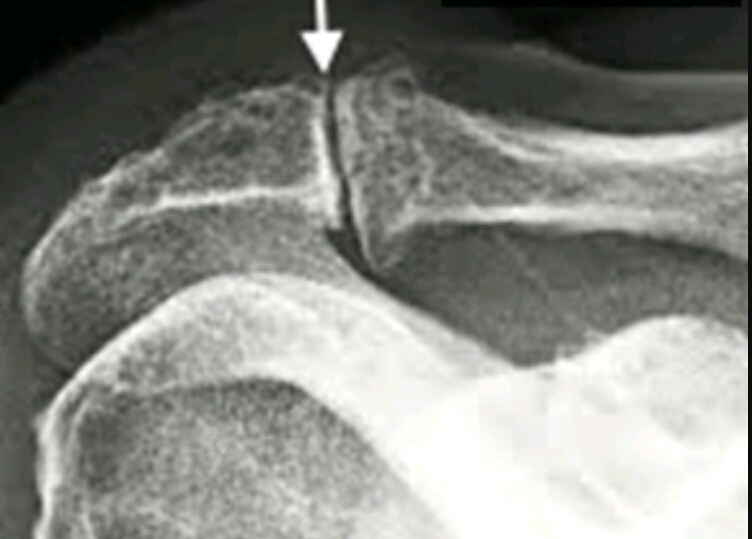

Name the features. What disease does this correlate with?

What can these features do to regular anatomy?

AC joint degeneration

osteophytes

osteophytes can impinge rotator cuff, leading to tendon calcification and superior migration of humerus